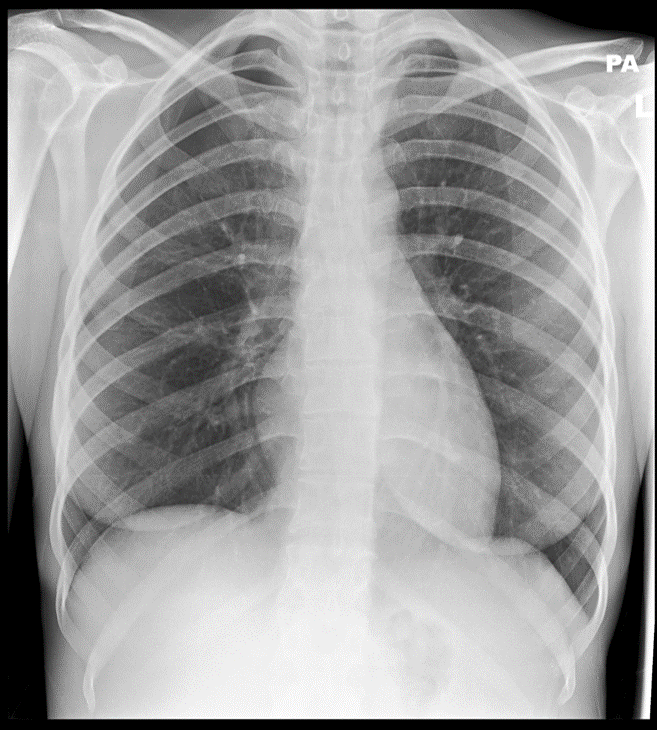

Cough for 3 weeks

Normal (3)